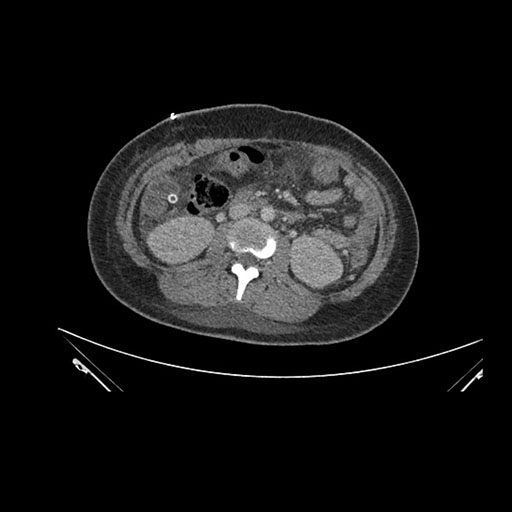

Axial Arterial

Axial Venous